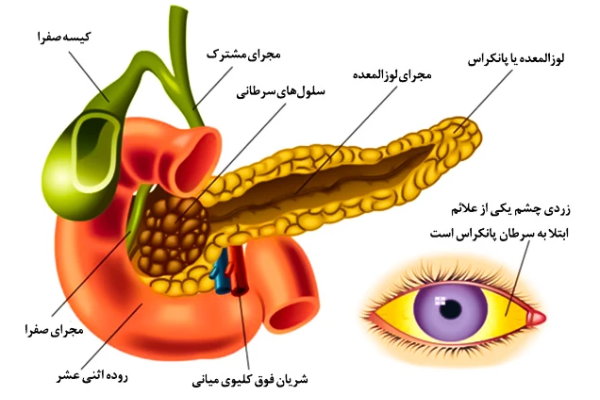

- زردی پوست و چشمها (یرقان): زمانی که تومور مجاری صفراوی را مسدود کند، صفرا در بدن تجمع پیدا میکند و باعث زرد شدن پوست میشود.

آیا همه بیماران دچار زردی میشوند؟

زردی بیشتر در تومورهای واقع در سر پانکراس دیده میشود که باعث انسداد مجاری صفراوی میشوند.